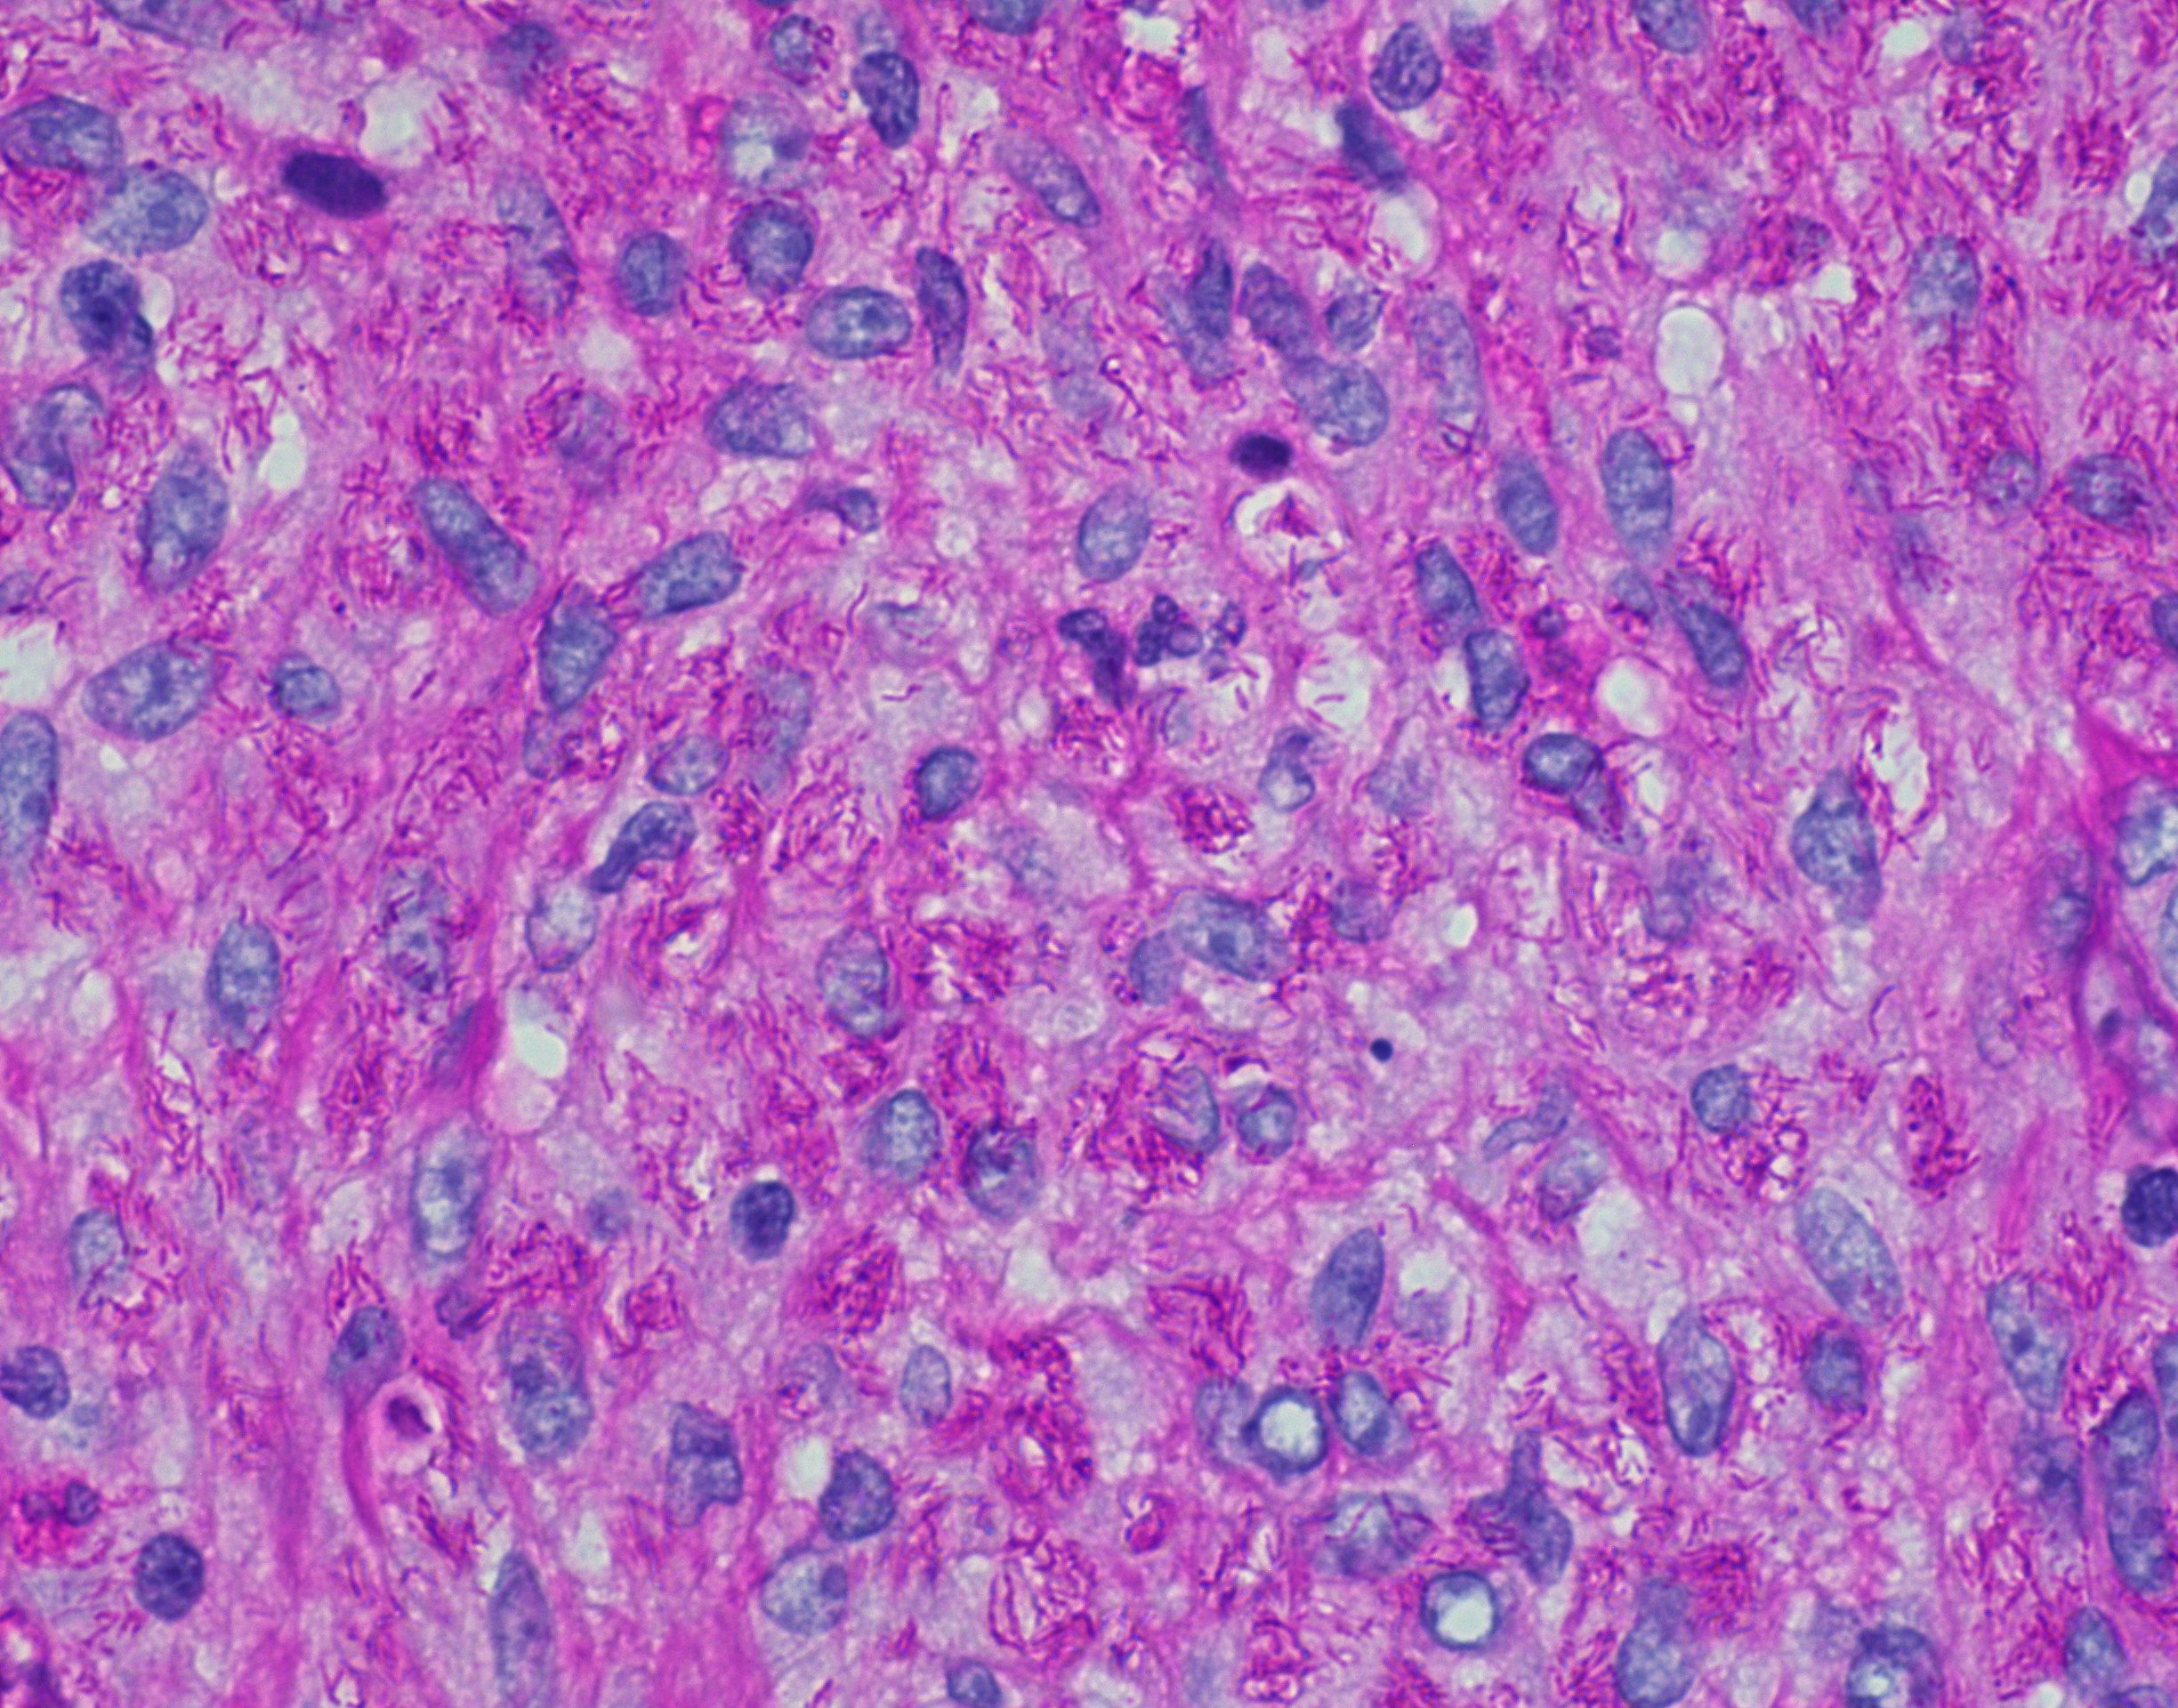

Microscopic (histologic) description

- Nodes show partial / complete effacement by storiform pattern of bland spindle cells, some with vacuoles

- Numerous vessels lined by plump endothelial cells, plasma cells and lymphocytes

- No multinucleated tumor cells, no foamy histiocytes

Microscopic (histologic) images

Contributed by AFIP and Chunyu Cai, M.D., Ph.D. (Case #532)

Positive stains